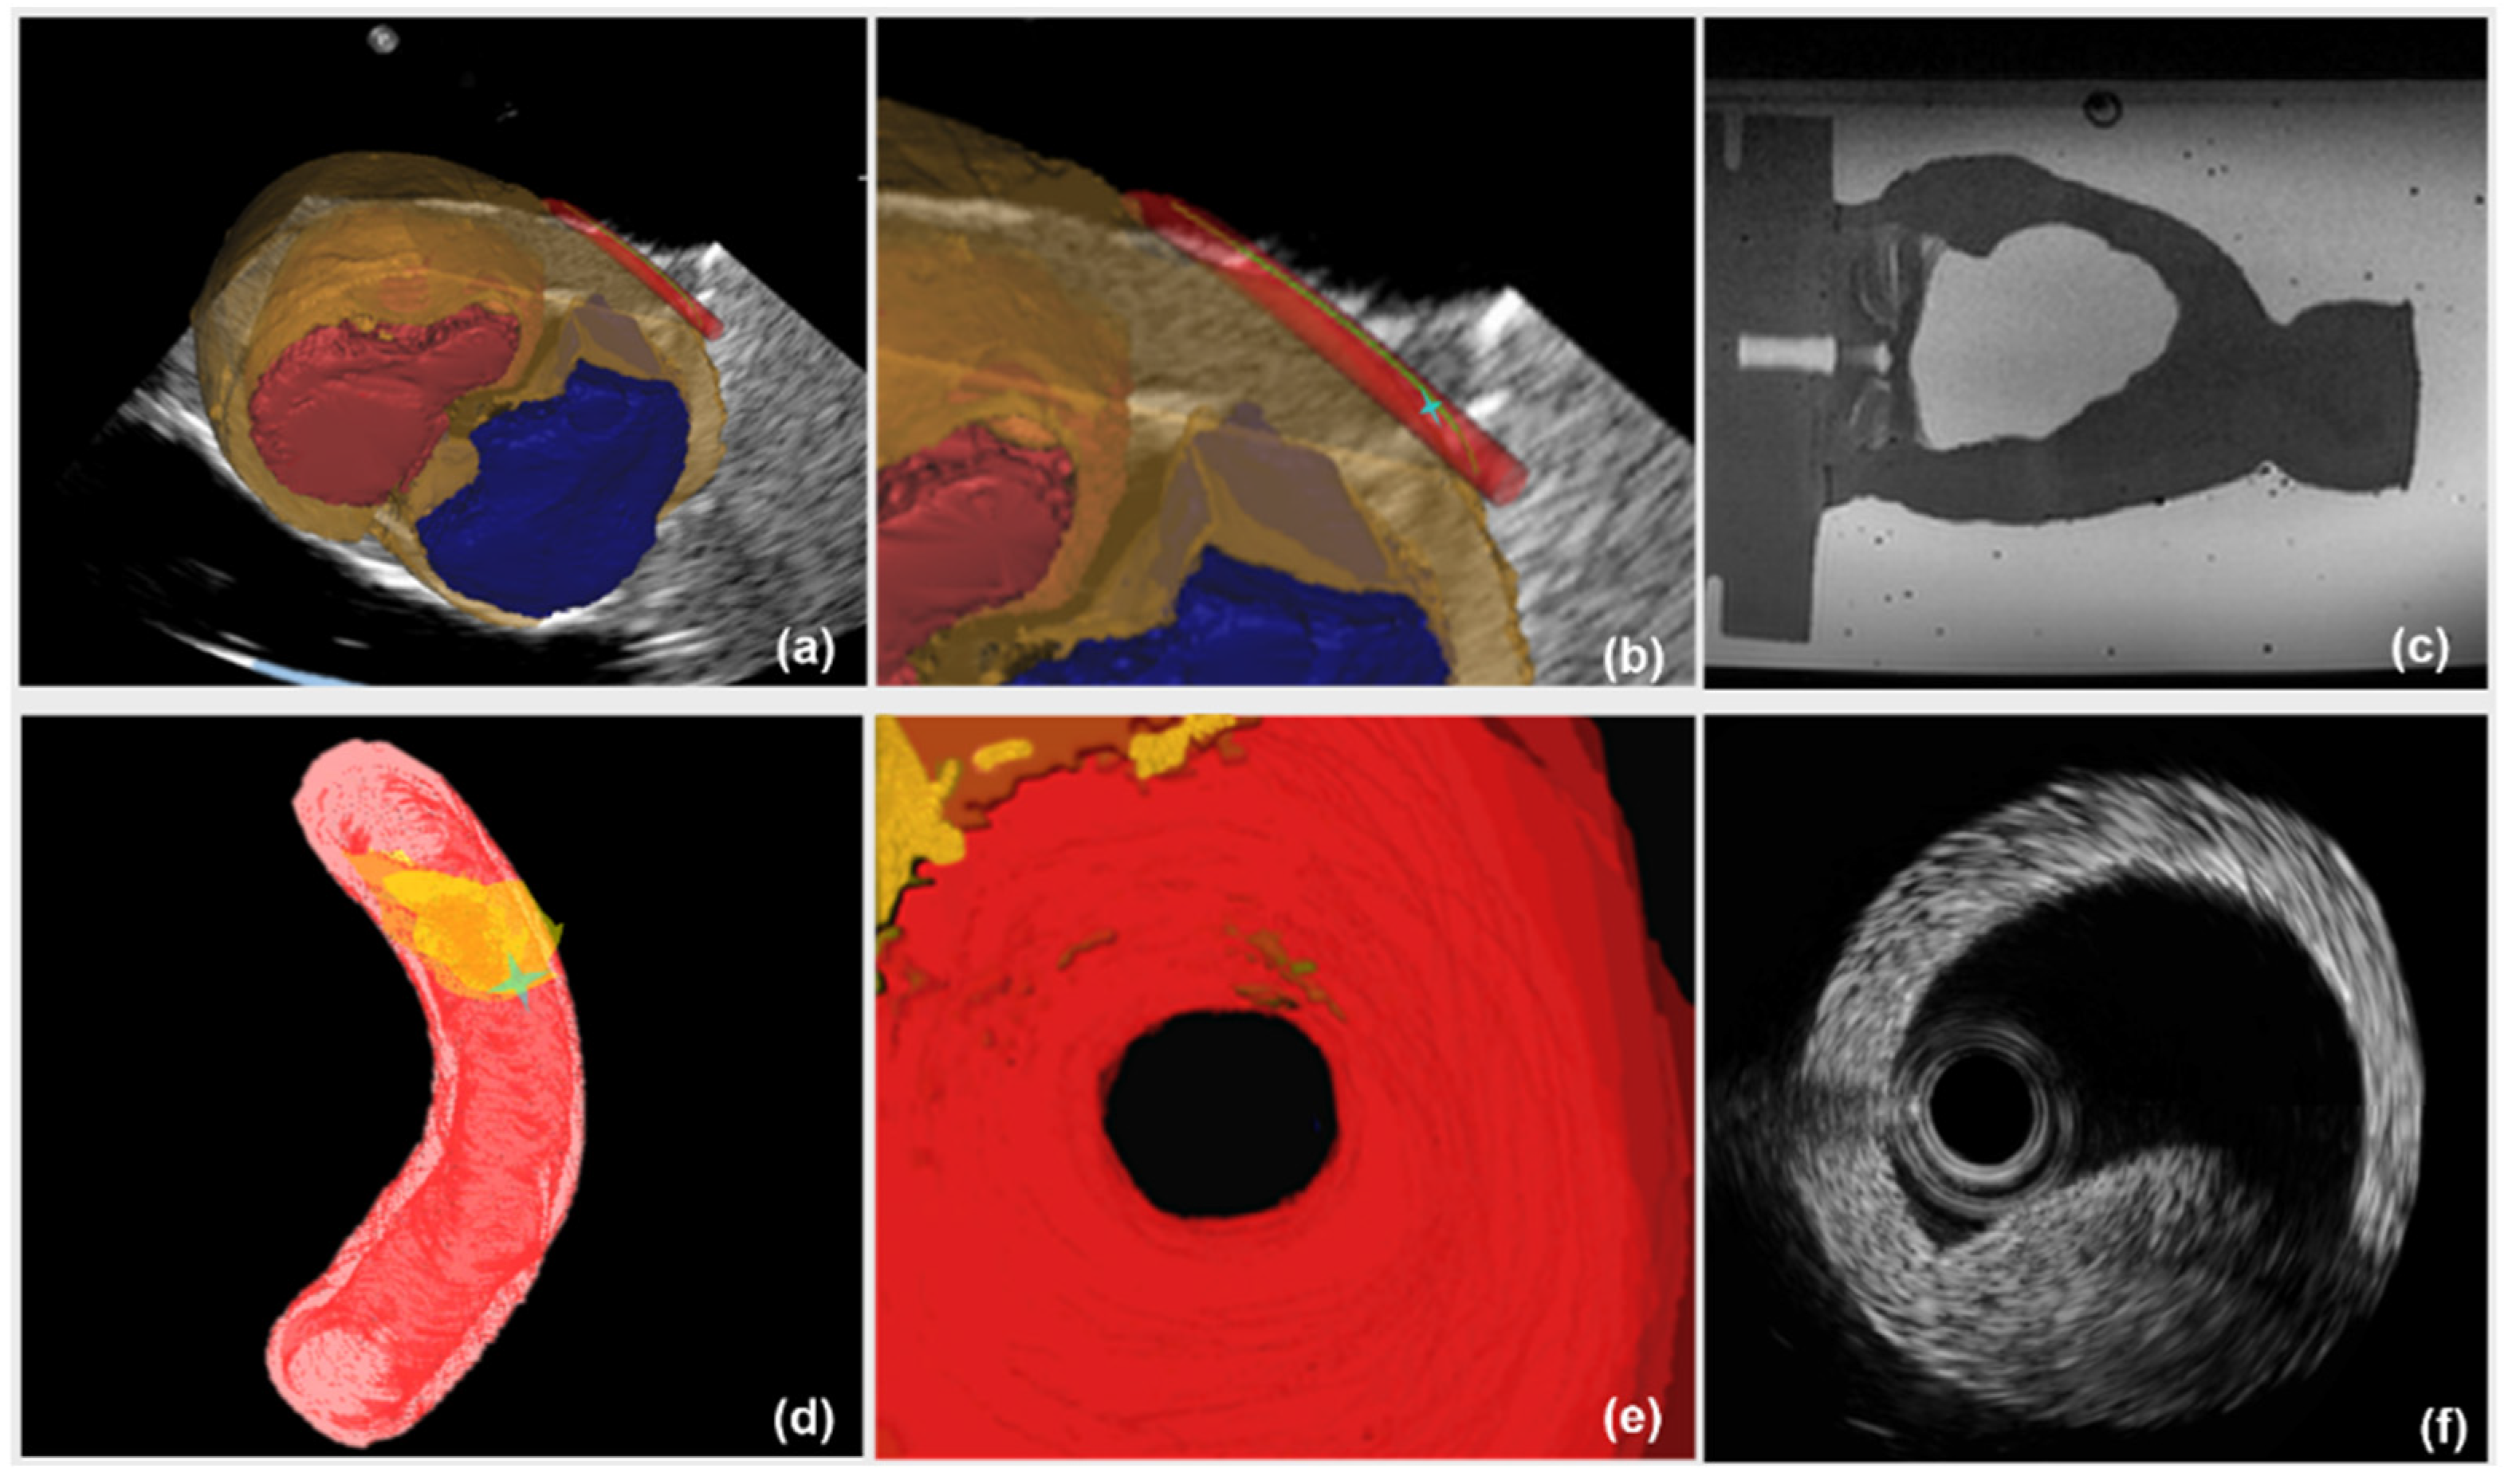

Accurate IVUS segmentation and borders detection can provide lesion location inside the vessel for local navigation. For clinical patients who need stent placements, the collected IVUS images contain information on the lesions but various artifacts exist. A segmentation method applicable for real patients is critical. Therefore, the performance of IVUS segmentation method was evaluated using 500 IVUS images from the sequences of ten patients. These patients’ IVUS sequences were collected in Navy PLA General Hospital, China (detailed information of patients is listed in supplementary material Table S1). The MA and lumen borders of 500 images had been manually delineated by an expert in IVUS images interpretation from the Navy PLA General Hospital. Examples of segmented lumen and MA borders of our method are illustrated in Figure 9. Segmentation accuracy was quantified by using standard measurements including Dice indexes and Hausdorff distance. The comparison results of proposed segmentation method and manual delineation are listed in Table 1.

The image guidance interface and information during the intervention are illustrated in Figure 10. Under the guidance of a global navigation map (Figure 10a–c), the relative position between interventional catheter and 3D cardiac structure is displayed intuitively to navigate the catheter to the target. However, there is the limitation that the morphological information of aortic model, especially the lesion’s position, is blurred (Figure 10c). On one hand, to evaluate the vessel reconstruction error of global information, we measured the average outer radius of manually reconstructed aortic model from global MR image, and compared the average outer radius with the actual outer radius of aortic phantom (4.5000 mm). We selected 40 transverses of the reconstructed aortic model to acquire an average outer radius. The resolution of MR images is 0.4871 mm and the acquired reconstruction error of global navigation is 1.1241 mm. On the other hand, the catheter was navigated to the target using global information, and the distance between the catheter arrival position and the target was measured by using coronal and sagittal X-ray projections images from C-arm (Fluoroscan Insight, HOLOGIC, Boston, MA, USA). This distance is treated as targeting error of global navigation (See Figure 11a) and the acquired targeting error is 2.8701 mm.

Comparatively, in the case of a global map plus local navigation information, the user can be guided to insert catheter along the preoperative planning path. Meanwhile, the local navigation information (Figure 10d–f), further provides the user with critical details of the target point. Firstly, to evaluate the vessel reconstruction error of local navigation information, we calculated the average outer radius of the automatically reconstructed aortic model from segmented IVUS images, and compared this average outer radius with the actual radius of aortic phantom. The resolution of IVUS images is 0.0175 mm and the acquired reconstruction error of local information is 0.2217 mm. Secondly, to evaluate the targeting error of catheter intervention, we captured coronal and sagittal X-ray projections when the catheter was navigated to the target by using global plus local information. These projections images are measured (See Figure 11b) and the acquired targeting error is 1.7214 mm. This experiment shows that the new US navigation system which integrates global and local information can improve upon the navigation system that relies on a global navigation map alone.

Local high-resolution navigation can reveal morphological characteristics of the aorta, especially the information on the target lesion. The vessel reconstruction error of local information is reduced by 80% compared to global information (error: 0.2217 mm versus 1.1241 mm). In addition, in the catheter intervention experiment, the targeting error of global navigation is 2.8701 mm. By adding the local high-resolution navigation information to global navigation, the targeting error reduces to 1.7214 mm. Thus, combining the large view of global navigation with the high accuracy of local navigation can provide surgeons with an intuitive 3D map and adequate lesion location for precise catheter intervention in stent deployment.

Figure 9. Segmentation examples of IVUS images; yellow and green contours denote the MA and lumen borders respectively (dotted lines denote detected borders by manual segmentation and full lines denote detected contours by proposed segmentation method, respectively).

Figure 10. Image guidance interface and information. (a) a global navigation map from 2D US-3D MR registration; (b) enlarged view of a global map at the region of aorta, green curve is the preoperative planning path, asterisk denotes the position of interventional catheter; (c) collected MR image; (d) local navigation information with morphological characteristics of aorta. Dark yellow volume is lesion; (e) virtual visual image from endovascular view; (f) collected IVUS image.